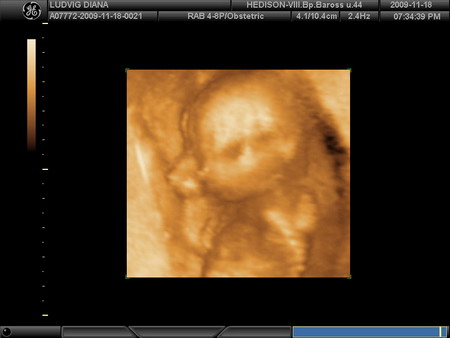

Drága kislányunk pofija a 18 hetes genetikai uh-n.